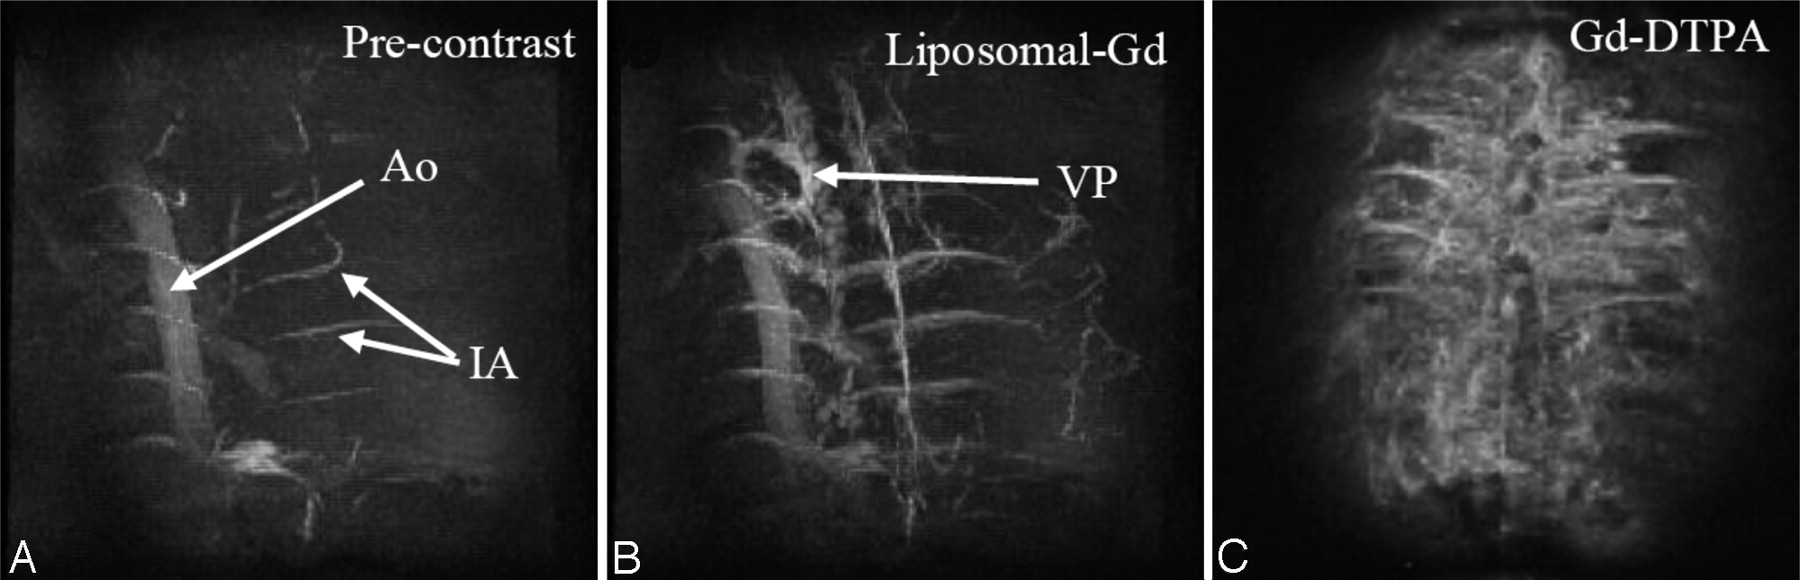

For the standard resolution study, MIP images of the thoracic spinal region in the coronal plane were generated from acquisitions obtained before and after the administration of liposomal-Gd and Gd-DTPA (Fig 1). The descending aorta and some of the intercostal arteries are visible on the precontrast image. The Gd-DTPA postcontrast image shows relatively poor image contrast between the vasculature and the surrounding tissue, as a result of enhancement of the extravascular tissues, presumably because of diffusion of the Gd-DTPA into the extracellular space. The scans acquired over the next 30 minutes showed no improvement in image quality. Conversely, the post–liposomal-Gd images showed clear vessel enhancement and negligible tissue enhancement. Given this good target-to-background contrast, more perispinal vasculature is demonstrable on the post–liposomal-Gd images. In fact, the intravascular enhancement observed is greater for the post–Gd-DTPA study, than for the post–liposomal-Gd study. However, the CNRs Gd-DTPA images were lower than for liposomal-Gd images (Table 1). (Subtle differences in image orientation in the postcontrast images in Fig 1 are of secondary importance compared with section-selection differences between the datasets, which were acquired using 2 different animals.)

Coronal MIP images of the thoracolumbar spine region acquired precontrast (A), post–liposomal-Gd (B), and post–Gd-DTPA (C). The images were acquired using the following parameters: TR/TE, 18.3/2.8 ms; flip angle, 30°; image matrix, 128 × 128 × 64; FOV, 41 × 28 × 25 mm; no. of signal intensity average, 1. The total scan time was 2.5 minutes. The descending aorta (Ao), and intercostal arteries (IA) are demonstrated in the precontrast image (A). The epidural venous plexus (VP) and more details about the intercostal arteries are demonstrated in post–liposomal-Gd image (B). The tissue enhancement due to diffusion of Gd-DTPA into the extravasacular space is shown in post-Gd-DTPA image (C). Post–liposomal-Gd and post–Gd-DTPA images were acquired in different animals.